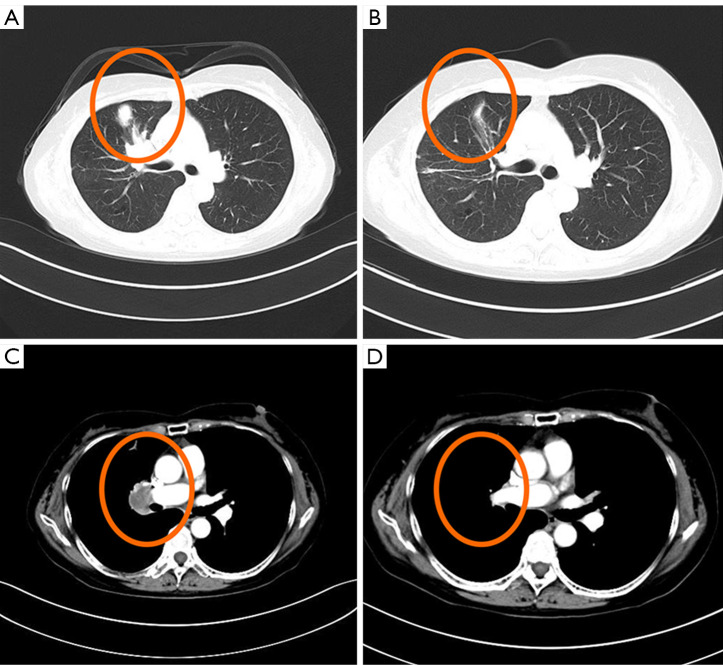

Case description: We report the case of a 65-year-old female patient with advanced lung adenocarcinoma (LUAD) who developed bone and adrenal gland metastases following treatment with gefitinib. Next-generation sequencing (NGS) of a biopsy specimen revealed the co-occurrence of MET amplification and EGFR exon 19 deletion mutation. The combined treatment of savolitinib and gefitinib effectively controlled the disease, resulting in a favorable long-term clinical outcome. With continued follow-up through April 2025, the patient has maintained progression-free survival (PFS) over 8 years. However, monitoring revealed the patient had grade 4 peripheral edema, and negative circulating tumor DNA (ctDNA), which necessitated a savolitinib dose reduction. Subsequent minimal residual disease (MRD) assessments and radiological scans revealed a remarkable therapeutic response with sustained efficacy.